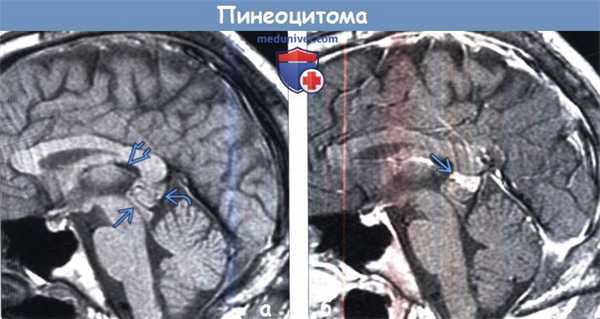

(а) На рисунке сагиттального среза изображены кистозное объемное образование эпифиза с уровнем раздела жидкость-жидкость и узловой компонент опухоли, расположенный по периферии образования, что характерно для пинеоцитомы. Значимый масс-эффект отсутствует. Питуицитомы могут являться случайными находками или выявляться при гидроцефалии.

(б) Бесконтрастная КТ, аксиальный срез: определяется классический пример пинеоцитомы. Обратите внимание на периферические кальцификаты «взрывного» характера в структуре этого мелкого образования, произрастающего из пинеальной области. Размеры опухоли едва превышают 1 см. Гидроцефалия отсутствует.2. КТ при пинеоцитоме:

(а) МРТ, Т1-ВИ, сагиттальный срез: определяется объемное образование с четкими границами, расположенное в пинеальной области и изоинтенсивное по отношению к паренхиме мозга. Образование оказывает умеренный масс-эффектна тектум, однако сильвиев водопровод интактен, а гидроцефалия отсутствует. Пинеальная опухоль располагается под внутренними мозговыми венами и валиком мозолистого тела.

(б) МРТ, постконтрастное Т1-ВИ, сагиттальный срез: у того же пациента определяется гетерогенный характер контрастирования пинеоцитомы с его наибольшей выраженностью в области верхнего узлового компонента.в) Дифференциальная диагностика: